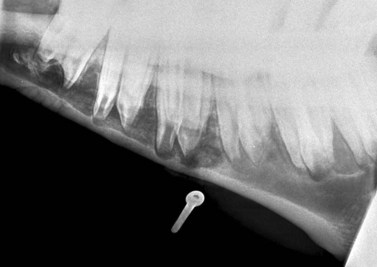

Odontogenic tumors

Tumors of dental-tissue origin are all rare, but may be more common in horses than in other species20 and are discussed in detail in Chapter 11. Five types of odontogenic tumors have been recorded in horses, and their radiological characteristics have been reviewed in detail.21 Ameloblastomas and ameloblastic odontomas can have a similar radiographic appearance.21 They are expansive, soft-tissue opacity masses containing lytic areas and sometimes areas of irregular granular calcification21 and often displace adjacent teeth (Fig. 13.42). Complex and compound odontomas are irregular, tumor-like masses of dental tissues in well differentiated forms (Fig. 13.43). Complex odontomas contain all the elements of a normal tooth but within a disorganized structure, hence radiologically they appear as multiple, small, lobulated radio-opaque masses within a well-defined cyst-like structure.20,21 In contrast, compound odontomas contain an orderly pattern of dental tissues which form recognizable tooth-like structures. Cementomas are very radio-opaque mineralized structures, often rounded in appearance and associated with chronically infected tooth apices (Fig. 13.41F) or their alveoli following extraction of the infected tooth.

image

Fig. 13.42 Ameloblastoma of the rostral mandible, which has displaced the 303 laterally and caused erosion of the 302 and 301 incisors. These tumors can have varying degrees of calcification – this one is well calcified.

(Radiograph courtesy of P.M. Dixon.)

image image image

Fig. 13.43 Radiograph (A) and CT images (B and C) of a compound odontoma in a 2-year-old TB colt.

(Images courtesy of J. Easley.)